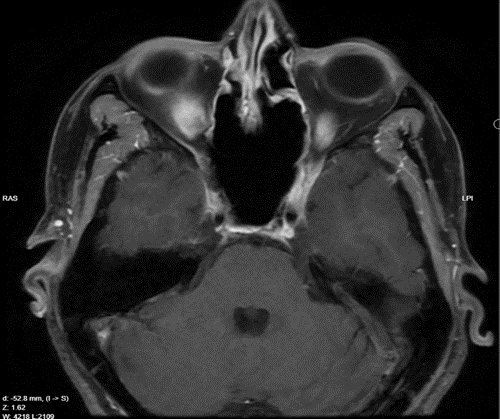

We report the case of a 45-year-old woman who presented with complaints of vision changes and dryness in her eye. Magnetic resonance imaging (MRI) revealed a large, homogeneously contrast-enhancing mass located in the sphenoid sinus, accompanied by evidence of bone remodeling at the skull base (Figure 1,2).

Figure 1: T1 MRI Axial view of the lesion

Figure 2